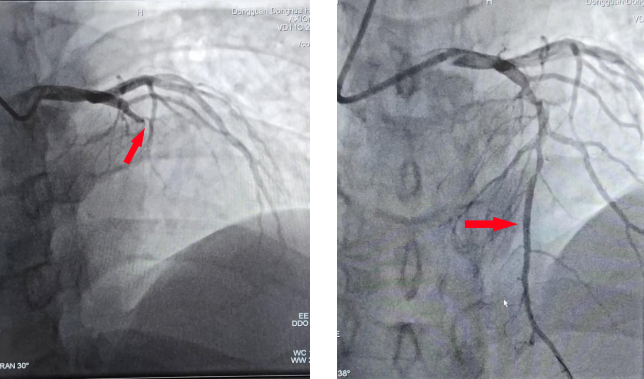

蜂蛹过敏引发心脏危机,争分夺秒紧急施救

2024-09-20